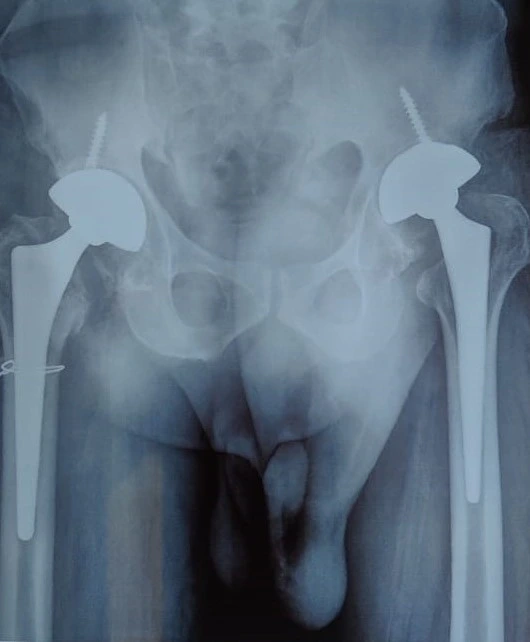

Quality and affordable healthcare has long been the essence in the field of medical sciences & treatment. Every patient expects an early diagnosis and a planned approach to treatment procedures with affordability and access to quality healthcare. Knee replacement, Hip replacement, Fracture treatment are being done by Dr.P.Sankaralingam at very affordable costs without compromising on quality.

Dr.P.Sankaralingam M.S(ortho)., DNB (ortho).,MNAMS is an experienced senior consultant Orthopaedic surgeon who does about 350 joint replacement surgeries per year in addition to treatment of Trauma cases.

• Hip & Knee Replacement and Revision Surgeries